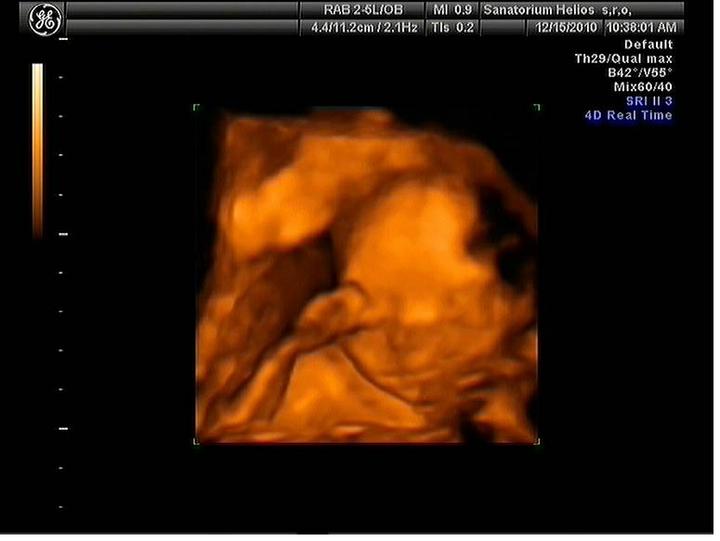

Jsme zpátky z dovolené, prcek v bříšku ani moc nezlobil🙂

Za 7 hodin uvidíme naši fazolku, nemůžu se dočkat a asi proto nemůžu spát. Strašně se těším. Snad bude vše v pořádku.